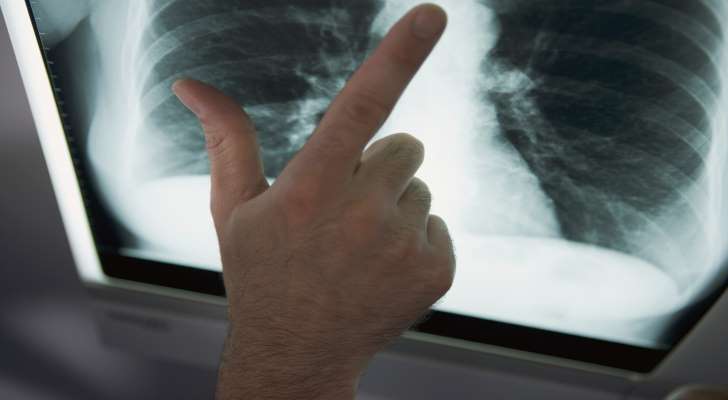

What Are the Symptoms of a Tuberculosis?

Finally, there are serious issues with breathing like shortness of breath and lack of oxygen in the lungs as the outcome of tuberculosis. Many other patients report pains in the chest and breathing problems, but when accompanied by other dangerous symptoms, it usually means that you have a Tuberculosis. It becomes impossible to do physical exercise and even minimal daily activities such as going shopping. Exhaustion appears in every case.